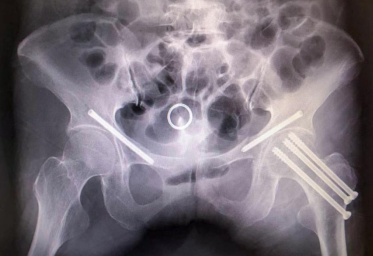

术中,骨科手术机器人先通过专用C型臂透视下取得骨盆和左侧股骨图像,在电脑上分别规划好最佳置钉路径后,机械臂随动运行调整到最佳角度,引导医生通过4个直径约1厘米的切口完成了空心螺钉的一次性精准置入,曹女士的手术在手术机器人与医生们的默契配合下顺利完成。

术中